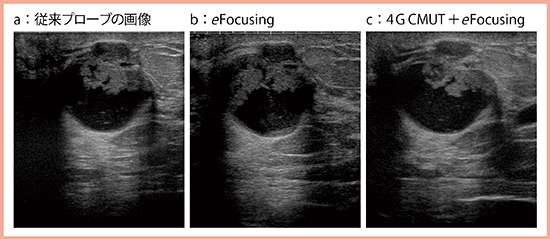

図3は線維腺腫であるが,eFocusingを適用した画像(b)では病変や境界が明瞭であり,シャープな印象である。大胸筋も深部まで明瞭に描出されており,画像全体にフォーカスが合っている。

図3 eFocusingの有無による描出の違い(線維腺腫)

実際に,囊胞内病変の画像(図5)を比較すると,従来プローブの画像(a)よりも,eFocusingを適用した画像(b)は全体がシャープとなり,4G CMUT+eFocusing(c)では明らかに粒状性が向上し,情報量が増えていることがわかる。

図5 4G CMUT+eFocusingによる囊胞内病変の描出